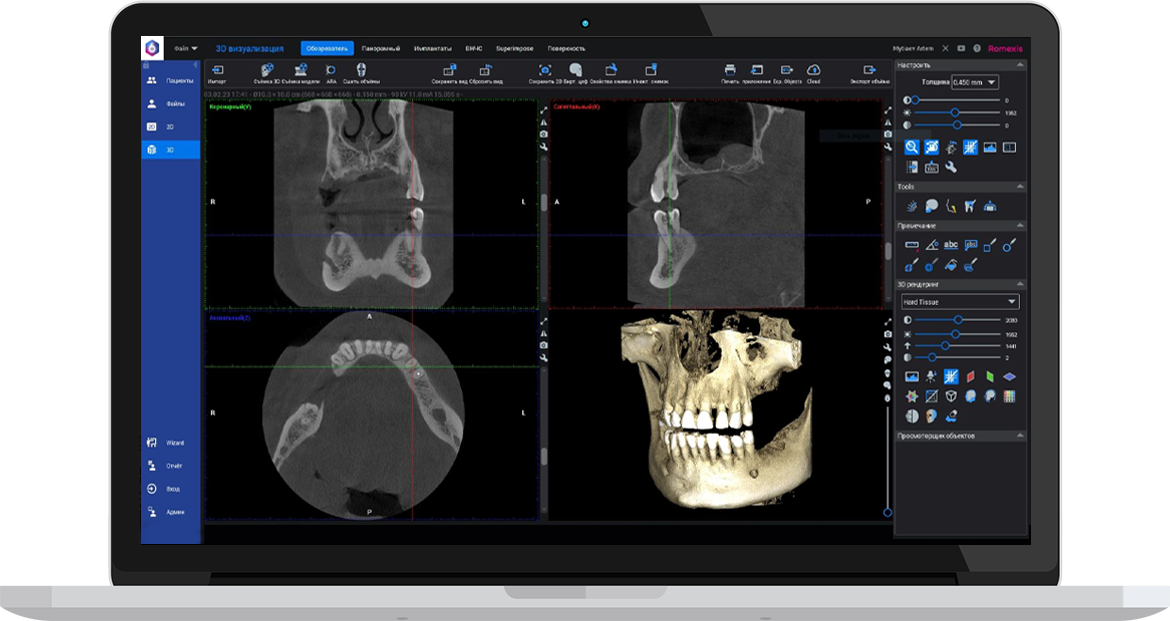

Ми використовуємо найсучасніше обладнання відомого виробника PLANMECA, що дозволяє отримувати високоякісні зображення за короткий час. Крім того, ми маємо власний сервер, на якому створюємо окрему скриньку для кожного лікаря, що забезпечує максимальну зручність та ефективність роботи.

Успішна імплантація починається з бездоганної діагностики. Томограф PLANMECA забезпечує

зображення в реальному масштабі 1:1 без геометричних спотворень, що критично важливо для

вибору розміру та позиції імплантату.

Ми економимо ваш час, надаючи повний пакет передопераційної підготовки:

Детальна розмітка: промальовування нижньощелепного каналу, візуалізація синусів та

ментальних отворів.

Точні виміри: визначення висоти та ширини альвеолярного гребеня, а також оцінка щільності

кісткової тканини в зоні майбутньої операції.

Всі дослідження миттєво доступні у вашій персональній папці на нашому захищеному сервері —

ви можете відкрити їх на будь-якому комп’ютері для демонстрації пацієнту або планування

операції.